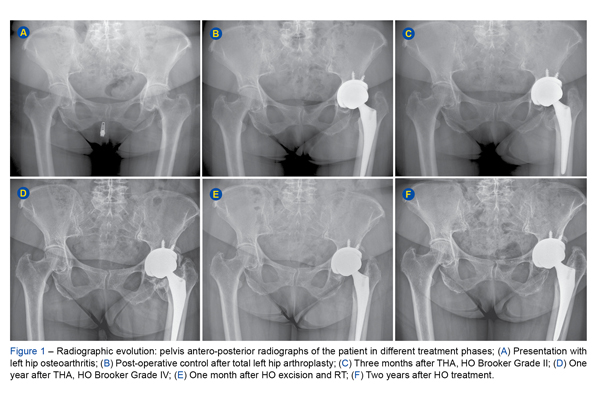

Heterotopic ossification (HO) is a well-known complication following total hip arthroplasty (THA), with an average incidence of 30%. Patients are classified according ...